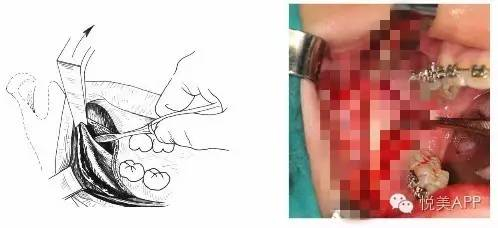

切开与显露

矢状与垂直骨切开

劈开下颌支

从矢状面劈开下颌支